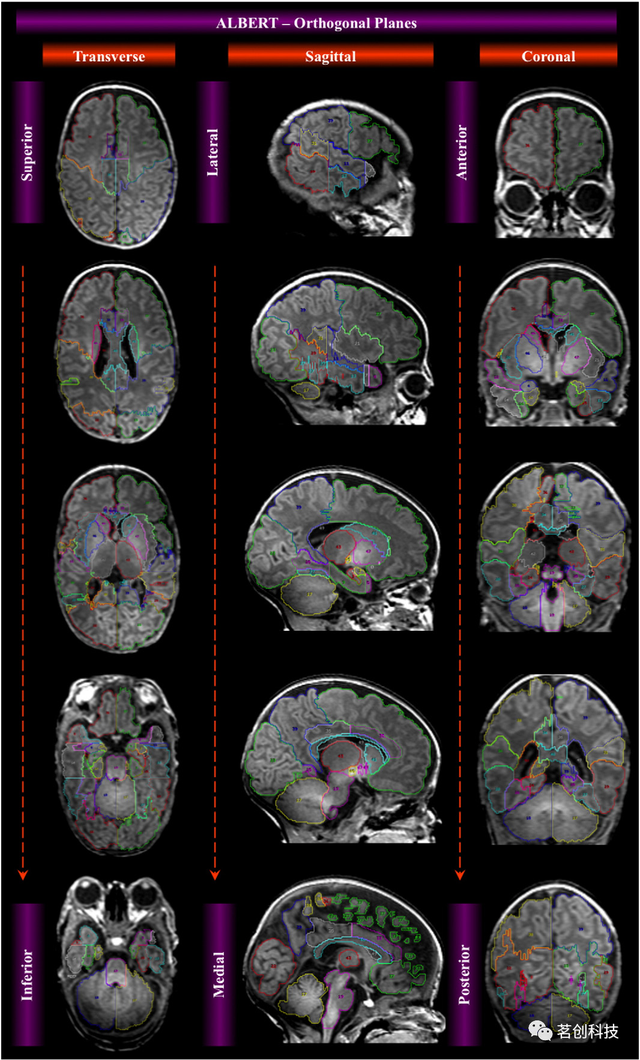

基于标签的脑ROI模板(ALBERT)

这是一组不同年龄的婴儿大脑图谱,其中包括来自20名足月和早产儿在矫正胎龄后第36-45周扫描的T1和T2加权图像,以及由50个手动划分的结构组成的分割图。

https://brain-development.org/brain-atlases/neonatal-brain-atlases/neonatal-brain-atlas-gousias/

来源:

Magnetic resonance imaging of the newborn brain: manual segmentation of labelled atlases in term-born and preterm infants.